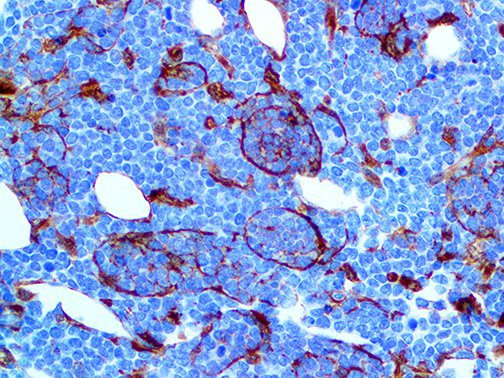

It is the ICU physician who is most likely to witness one of the deadliest manifestations of the abnormal immunological response, the cytokine storm syndrome (CSS). This response is also referred to by some as the cytokine release syndrome (CRS). CSS is characterized by continuous activation and expansion of macrophage and lymphocyte populations, which secrete large amounts of cytokines, causing the cytokine storm. This massive cytokine release is akin to hemophagocytic lymphohistiocytosis (HLH) disease, a syndrome characterized by initial unchecked and persistent activation of cytotoxic T lymphocytes and NK cells.

Clinical and laboratory manifestations of HLH include fever, enlarged liver and/or spleen, neurologic dysfunction, coagulopathy, liver dysfunction, cytopenias (i.e., low levels of erythrocytes, leukocytes, and/or platelets), hypertriglyceridemia, hyperferritinemia, hemophagocytosis, and eventually diminished NK cell activity as the immune system becomes progressively paralyzed. HLH can be familial (primary HLH) or secondary to another disease process (sHLH), such as rheumatic disease, in which it is referred to as macrophage activation syndrome (MAS, characterized by elevated ferritin).